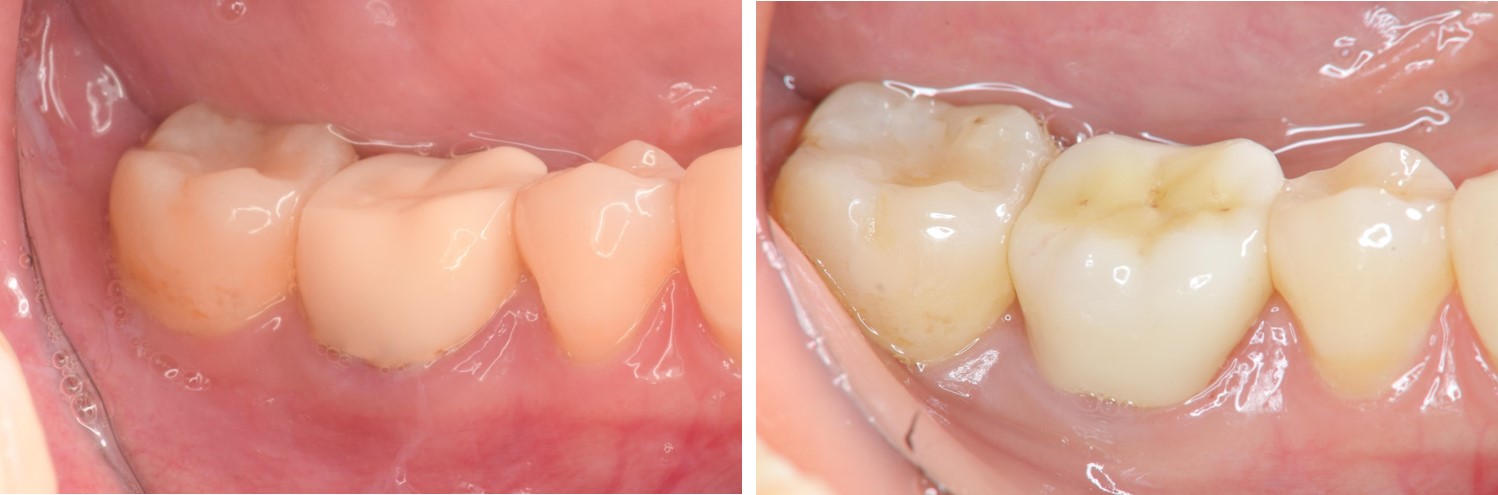

術前、術後比較

治療後,牙周咬合良好

治療後,密合度良好